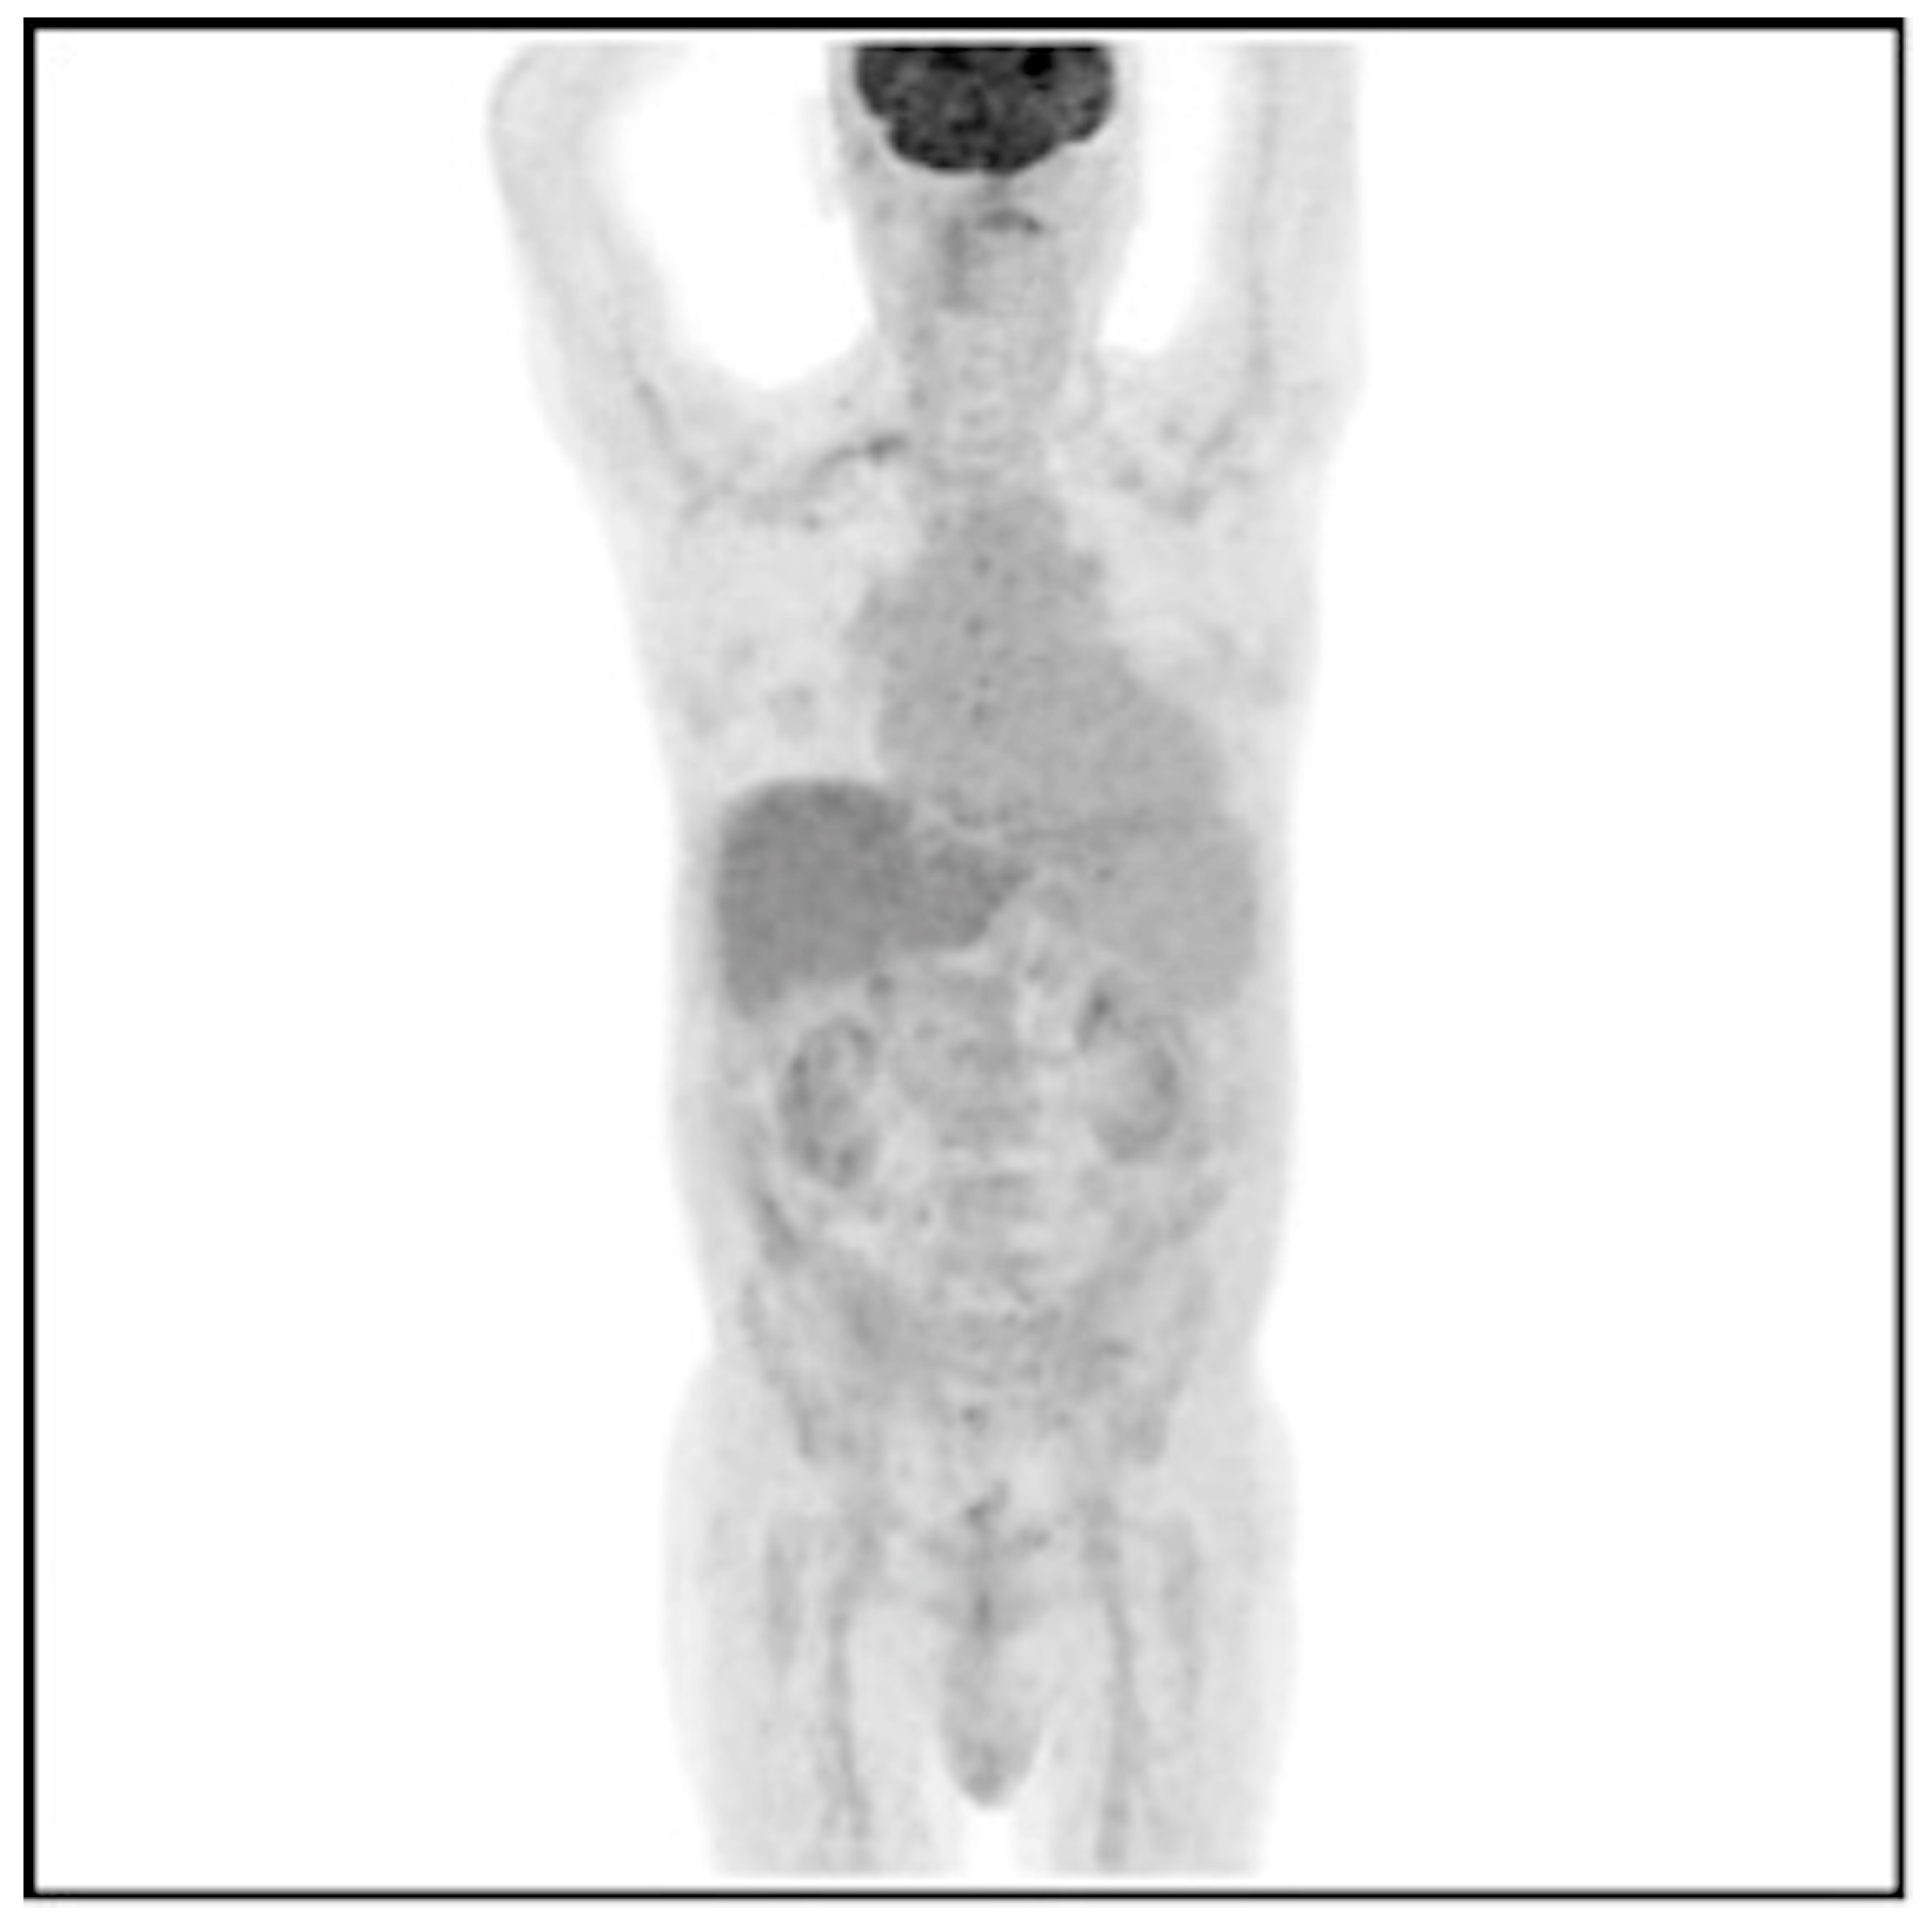

3.2. Results of the 18F-FDG PET/CT Examination Analysis